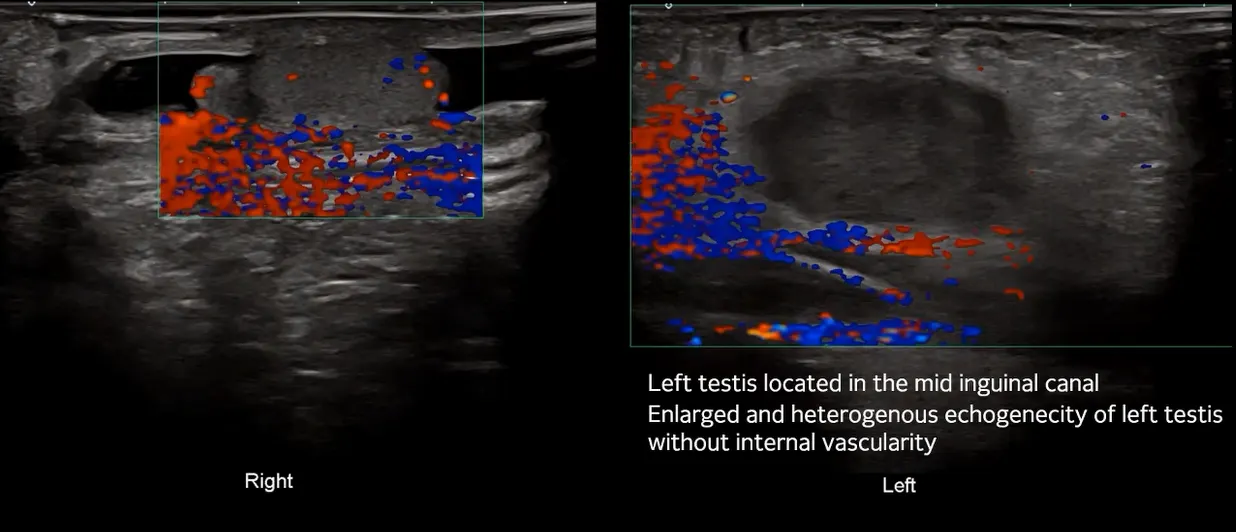

E3. Undescended testicular torsion

(2) Doppler US

enlarged testis, decreased or absent flow